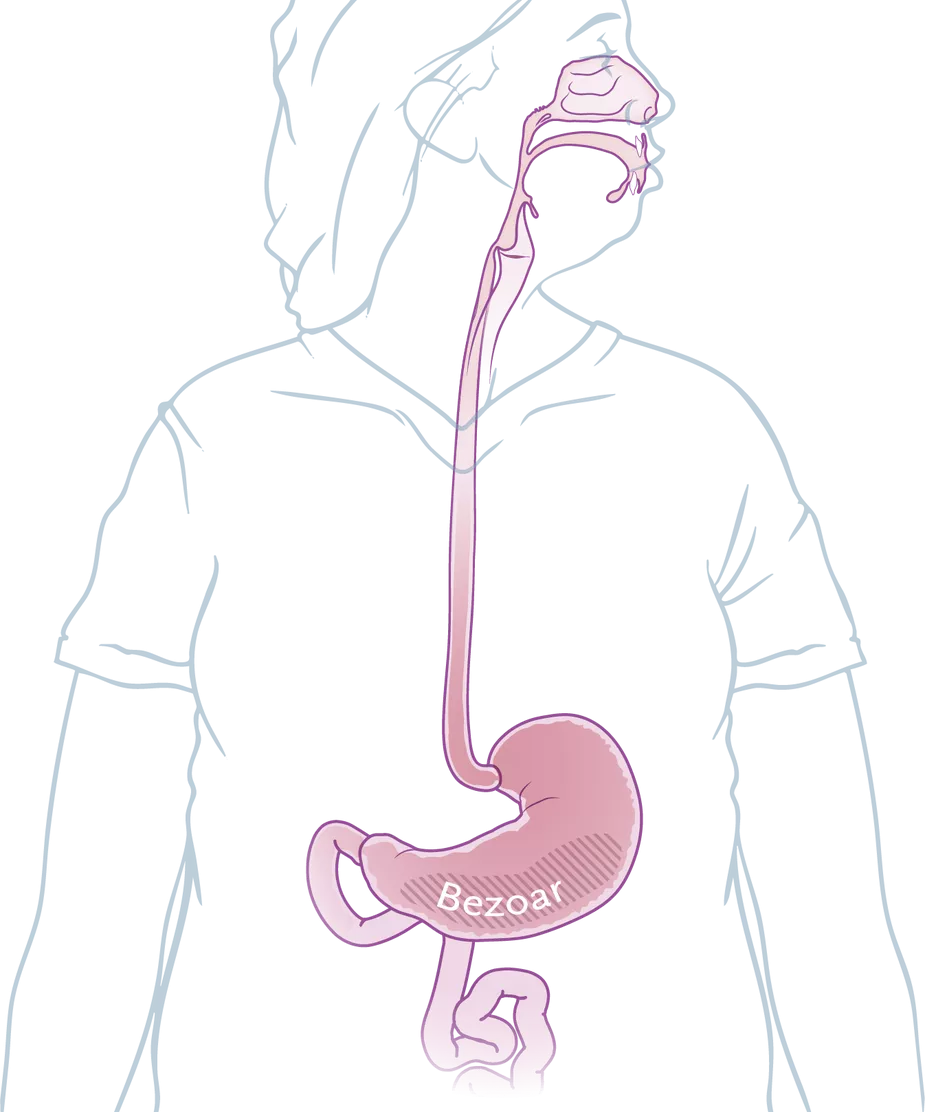

被叫做结石的,都是空心器官里出现的、本来不该有的硬团块。胃石(Gastric

Bezoars),也就是没有被消化的物质在胃里凝集形成的团块。通常,胃石不如其他结石坚硬,但韧性比较强。

胃石形成,主要是因为难消化和排不出。难消化的,包括柿子、山楂、某些药物和毛发等异物。排不出是指胃肠功能不足,难以把胃内物质碾碎推到肠道里,原因可能在胃肠、糖尿病、自主神经病变或者影响胃动力的药物(如三环类抗抑郁药,以及本患者使用的司美格鲁肽、缓解腰背痛的阿片类强效镇痛药)。

左滑查看更多图片:胃石示意图、手术中看到的毛发性胃石、CT检查中的胃石 | 参考文献[1]